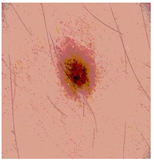

![]() | ![]() | ![]() | ![]() |

| Img1 | --- Pixel Intensity (0–255) ---> | ||

| Original Image | Th2 | Th3 | Th4 | Th5 |

|---|---|---|---|---|

![]() Img1 | ![]() | ![]() | ![]() | ![]() |